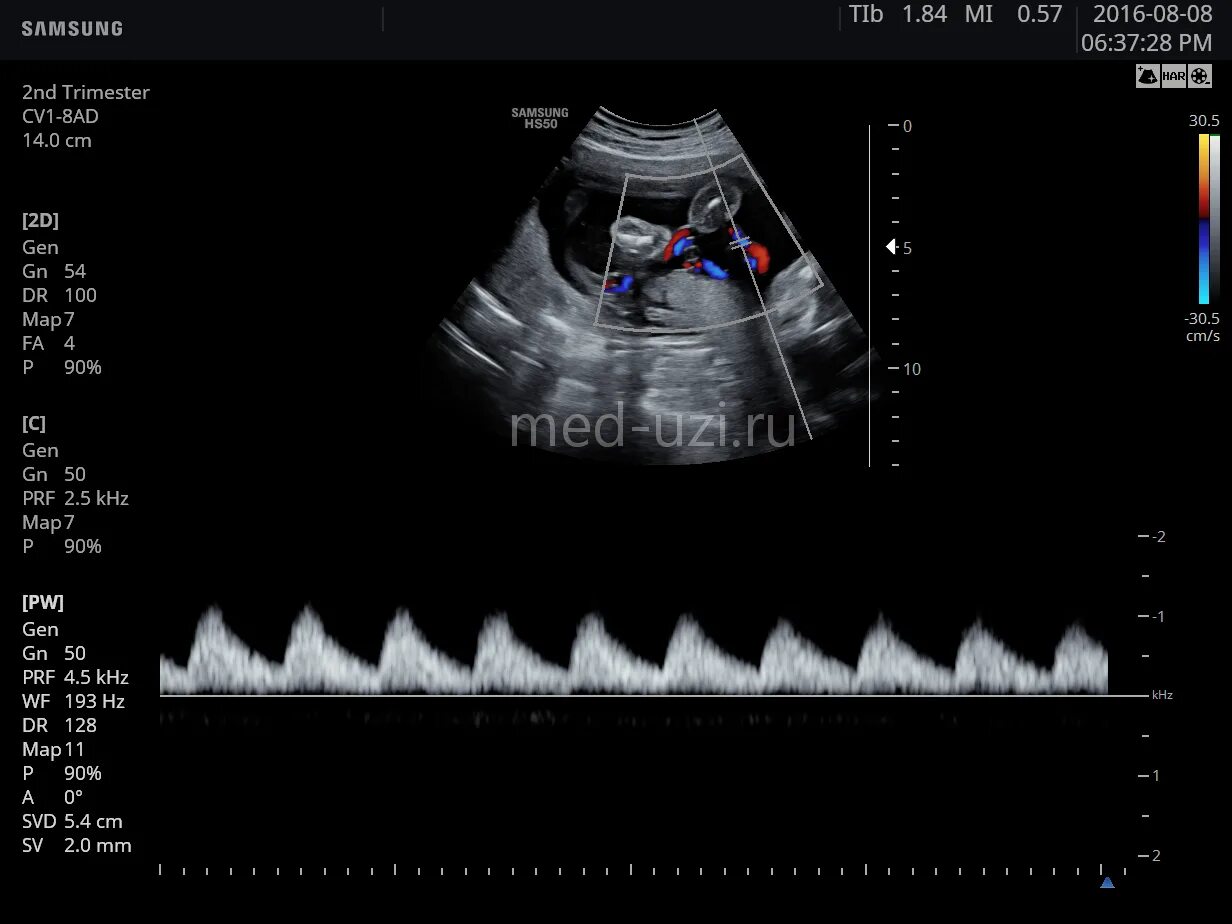

Режимы узи аппарата